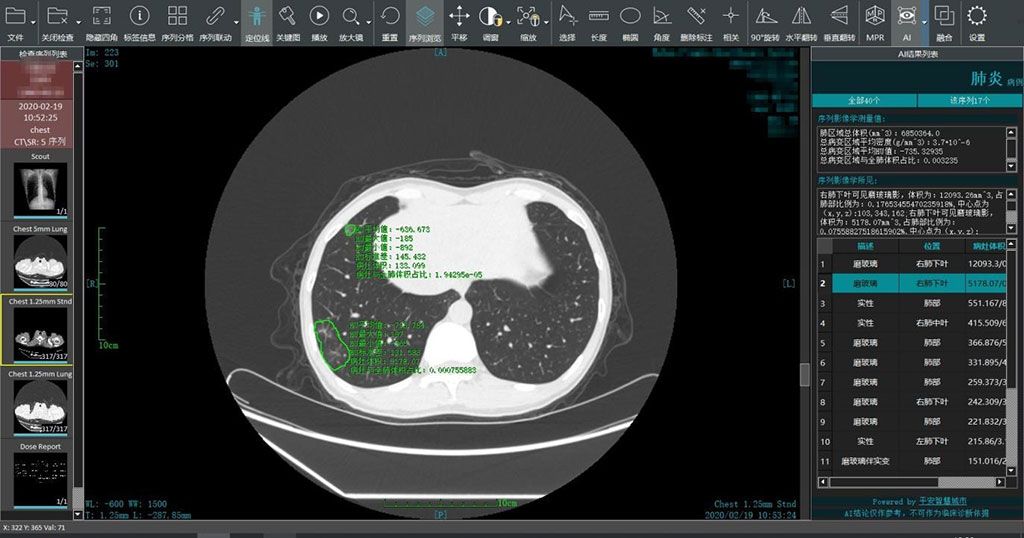

Imagen: Un sistema inteligente de lectura de imágenes genera análisis rápidos en áreas epidémicas (Fotografía cortesía de Ping An Smart Healthcare)

Un sistema de lectura de imágenes basado en inteligencia artificial (IA) podría proporcionar un diagnóstico y tratamiento más tempranos de pacientes con sospecha de enfermedad por coronavirus 2019 (COVID-19).

El sistema inteligente de lectura de imágenes COVID-19 de Ping An Smart Healthcare (SHENZHEN, China) utiliza un motor de IA para realizar un análisis comparativo de imágenes múltiples de tomografías computarizadas (TC) del mismo paciente para medir los cambios en las lesiones El sistema inteligente de lectura de imágenes de IA también admite imágenes remotas realizadas por profesionales médicos fuera de las áreas epidémicas, lo que ayuda a rastrear el desarrollo de la enfermedad. Las instituciones médicas que requieren servicios inteligentes de lectura de imágenes COVID-19 pueden obtener acceso en plataformas de nube públicas o privadas o en las instalaciones.

Ping An Smart Healthcare pone el software a disposición de casi 800 millones de personas en más de 70 ciudades de China y el sudeste asiático afiliadas a la compañía. El sistema inteligente de lectura de imágenes también se puede adaptar rápidamente para trabajar directamente con equipos de TC (con la ayuda de los fabricantes) para ayudar a diagnosticar el brote de COVID-19. A nivel individual, se puede usar para evaluar el tratamiento y el pronóstico de pacientes infectados, ayudando a los médicos a diagnosticar, clasificar y evaluar a los pacientes con COVID-19 de manera rápida y efectiva.

“Desde su lanzamiento, el sistema inteligente de lectura de imágenes ha brindado servicios a más de 1.500 instituciones médicas. Más de 5.000 pacientes recibieron servicios inteligentes de lectura de imágenes de forma gratuita. El sistema puede generar resultados de análisis inteligentes en alrededor de 15 segundos, con una tasa de exactitud superior al 90%”, dijo Geoff Kau, copresidente y director de estrategia de Ping An Smart City”. En comparación, a los radiólogos les toma alrededor de 15 minutos leer las imágenes de TC de un paciente sospechoso de contraer el COVID-19”.

“Los pacientes con COVID-19 necesitan múltiples tomografías computarizadas durante el tratamiento. Comparar múltiples imágenes es una tarea que lleva mucho tiempo y no se puede completar manualmente con exactitud”, dijo Xiao Jing, MD, científico jefe de Ping An. “Utilizando el sistema inteligente de lectura de imágenes COVID-19 de Ping An Smart Healthcare, se puede mejorar efectivamente la exactitud del diagnóstico y la eficiencia de lectura de imágenes del médico”.

COVID-19 generalmente se manifiesta en la TC con opacidades pulmonares bilaterales consolidadas y de vidrio esmerilado. Las opacidades nodulares, el patrón de pavimentación loca y una distribución periférica de la enfermedad pueden ser características adicionales útiles en el diagnóstico temprano. Por otro lado, la cavitación pulmonar, los nódulos pulmonares discretos, los derrames pleurales y la linfadenopatía están característicamente ausentes.